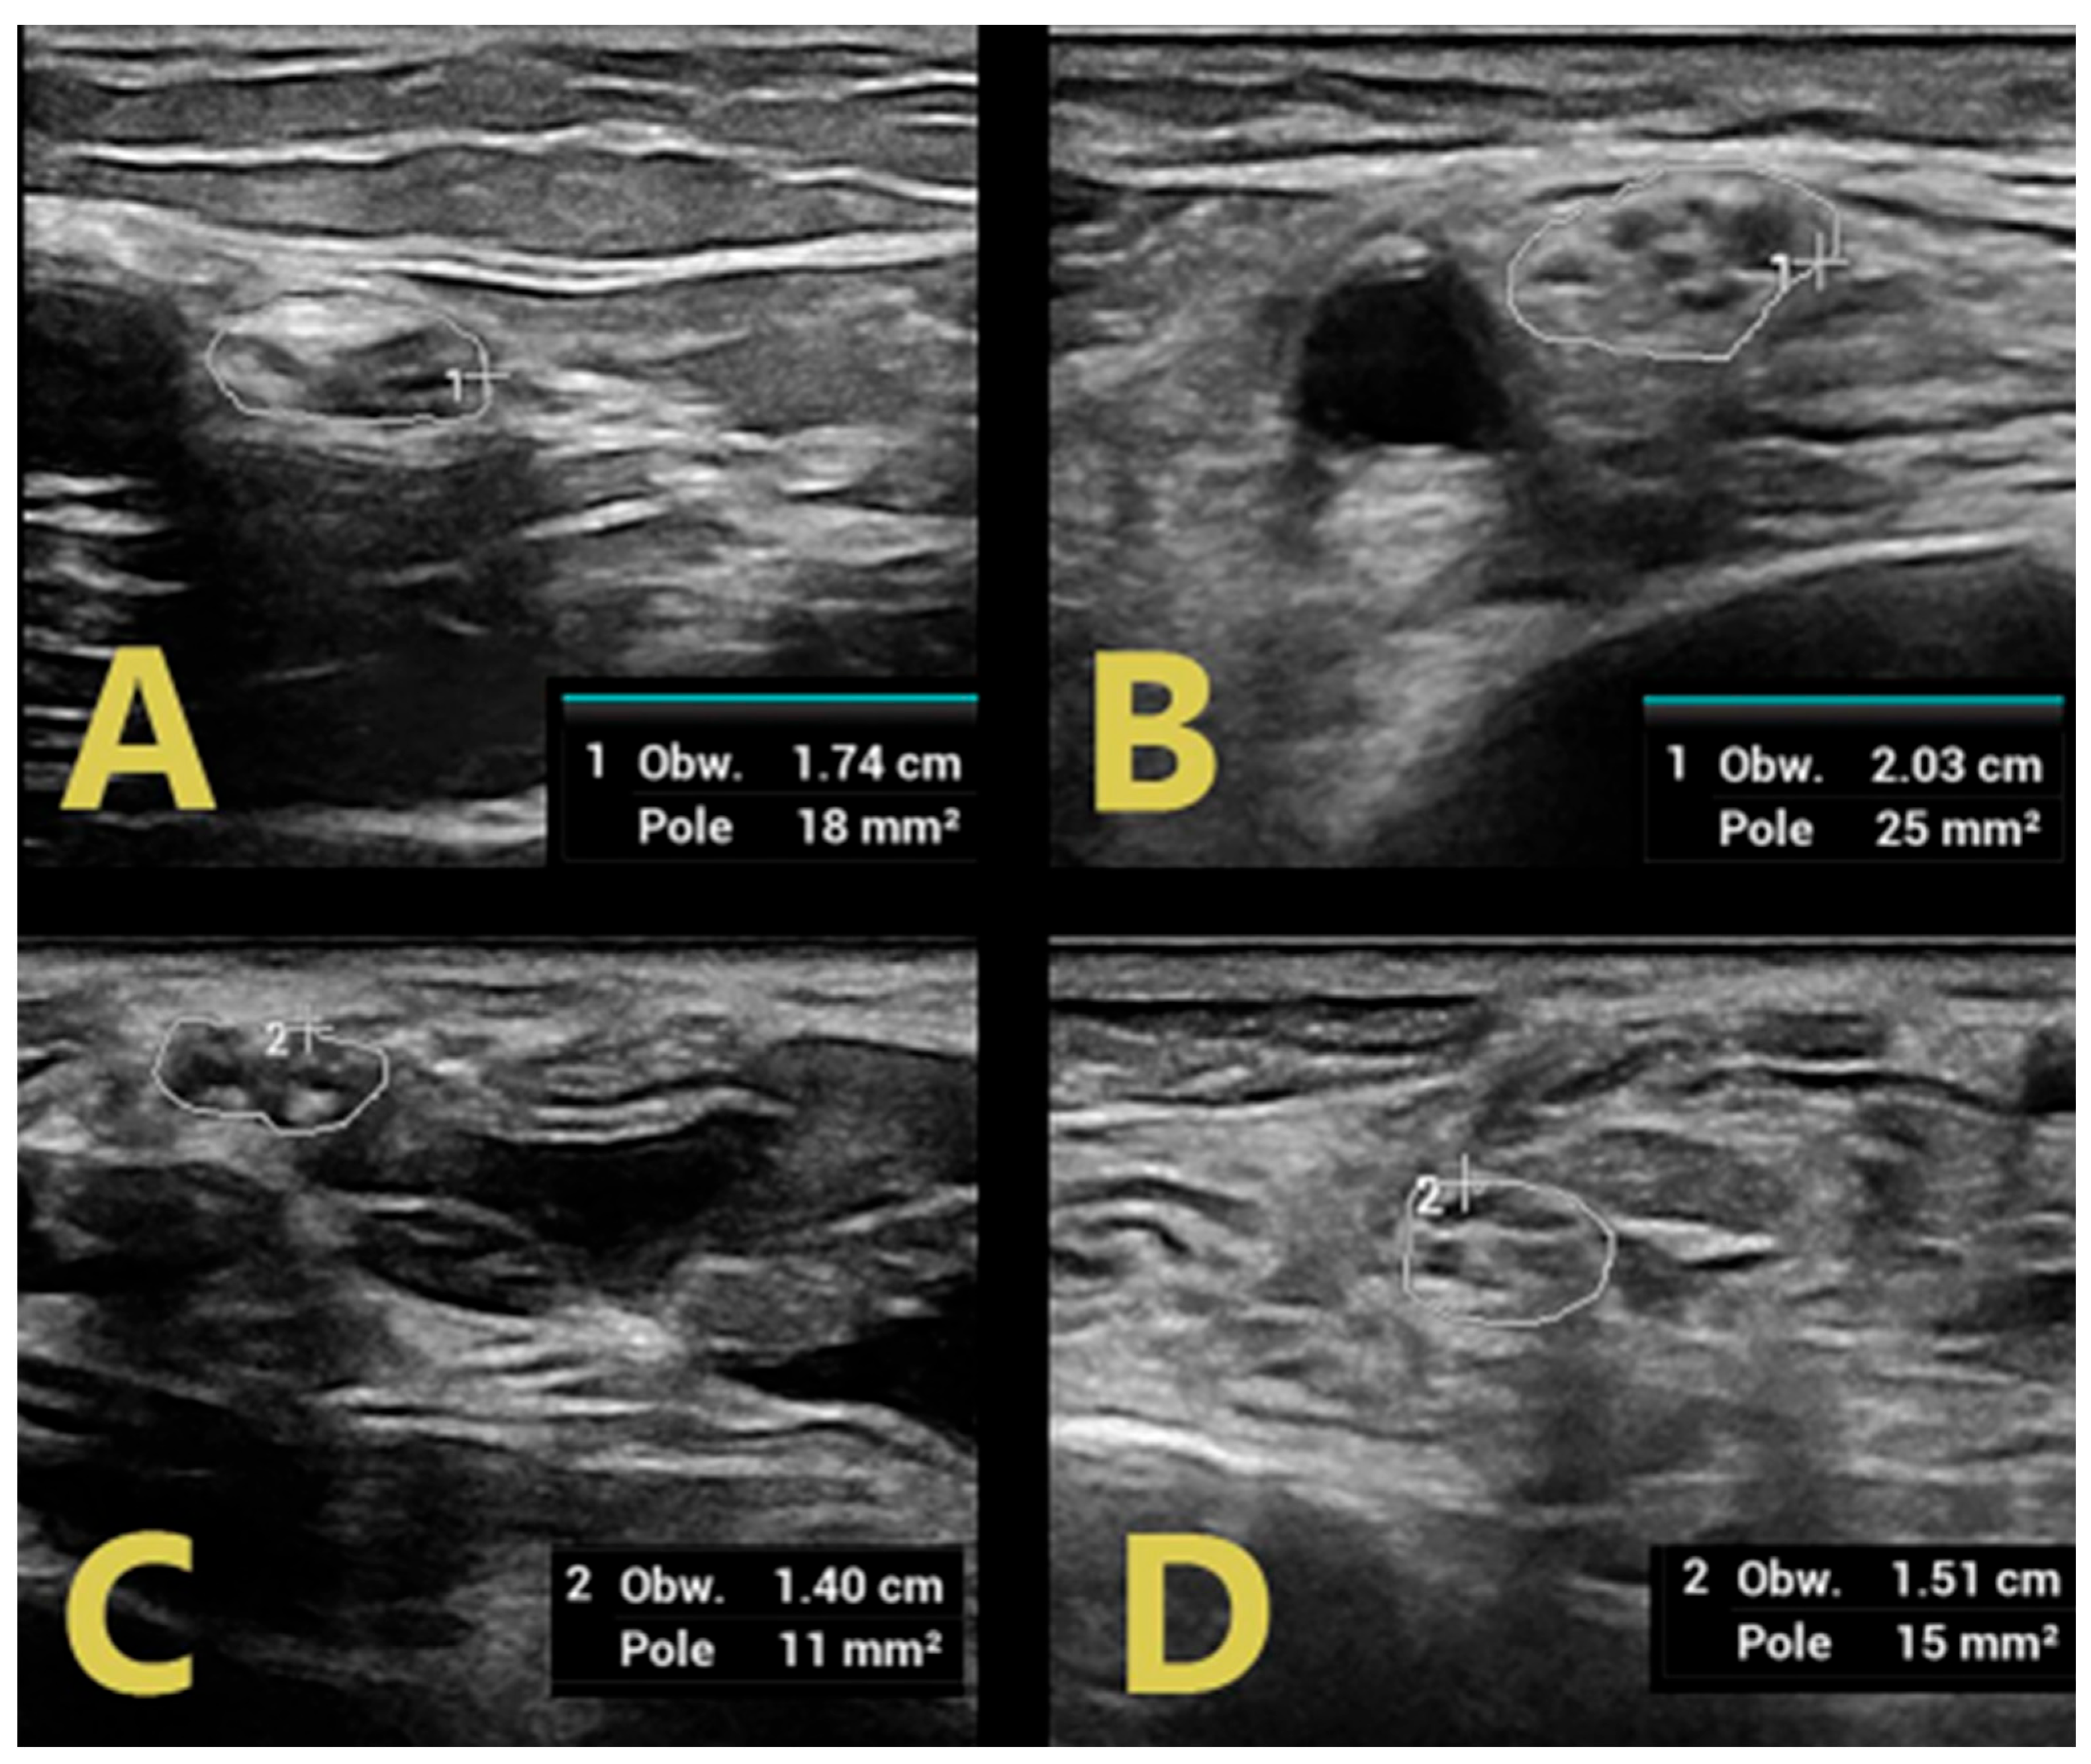

| SM | >6 months | - | 3/5 (ataxia) | ↑ CSA RMN, RUN, SBRRN ↑ C5 LAX CSA ↑↑ C6 | ↑↑ CSA RTN, RPN, ↑ CSA RSN | ↑ duration LMR | ↑ duration RMP |

| LAX CSA ↑ CSA VN | |||||||

| DJ | 17 months | - | 3/5 | ↑↑ CSA LMN ↑ CSA LUN ↑ C5 LAX CSA ↑↑ C6 LAX CSA ↑ CSA VN | ↑↑ CSA LTN, LPN, ↑ CSA LSN | ↑ duration LMM | ↑F latency LMT |

| DR | 6 months | - | 3/5 | ↑↑ CSA RMN ↑ CSA RUN ↑ C5 LAX CSA ↑↑ C6 LAX CSA ↑ CSA VN | ↑ CSA RTN, RPN, RSN | ↑ F latency RMT, LMT | |

| SZ | >5 months | - | 2/5 | ↑ CSA RMN, RUN ↑ C5 LAX CSA ↑↑ C6 LAX CSA ↑ CSA VN | ↑↑ CSA RTN, RPN, RSN | F wave absence RMT, LMP | |

| WJ | 17 months | - | 3/5 | ↑↑ CSA RMN ↑ C5 LAX CSA ↑↑ C6 LAX CSA ↑ CSA VN | ↑↑ CSA RTN, RPN, RSN | ↑ duration RMP, RMT | |

| BA | 6 months | 4/5 | 3/5 | ↑↑ CSA RMN, RUN ↑ C5 LAX CSA ↑↑ C6 LAX CSA ↑ CSA VN | ↑↑ CSA RTN, RPN, RSN | ↑ duration RMU | ↑ duration RMT |

| BD | 14 days | - | 2/5 | ↑ C5 LAX CSA ↑ C6 LAX CSA | ↑ CSA LTN, LPN | ↑ duration RMU, LMP | F-wave absence RMP |

| SMi | 4 days | 4/5 | 2/5 | ↑↑ CSA RMN ↑ C5 LAX CSA ↑ C6 LAX CSA | ↑ CSA RTN, | ↑ duration RMU | ↑F latency RMP, LMP ↑ duration RMP, LMP, RMT |

| LW | 6 weeks | - | 3/5 | ↑↑ CSA RMN, ↑ RUN ↑ C5 LAX CSA ↑ C6 LAX CSA | ↑ CSA RTN, RPN | ||